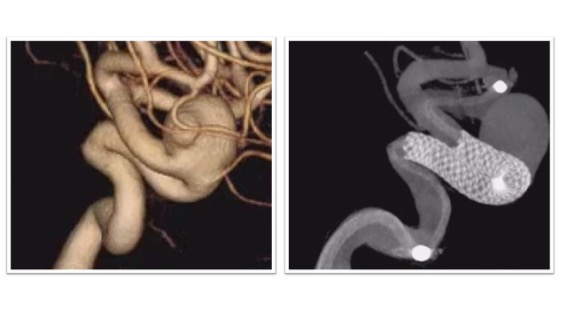

フローダイバーター治療実例(*患者様の許可を得て掲載しています)

大型内頸動脈(IC)動脈瘤

大型IC動脈瘤に対してフローダイバーターによる治療を実施。フローダイバーターは動脈瘤の根本をカバーする形で留置されました(右図)。術後は抗血小板薬の内服がしばらく必要となりますが、動脈瘤はその後半年ほどで閉塞しています。